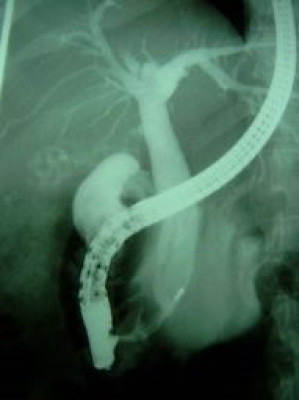

Coledocolitiasis múltiple y extracción

Envíado por Dr. Carlos Miguel Zavaleta Consuegra